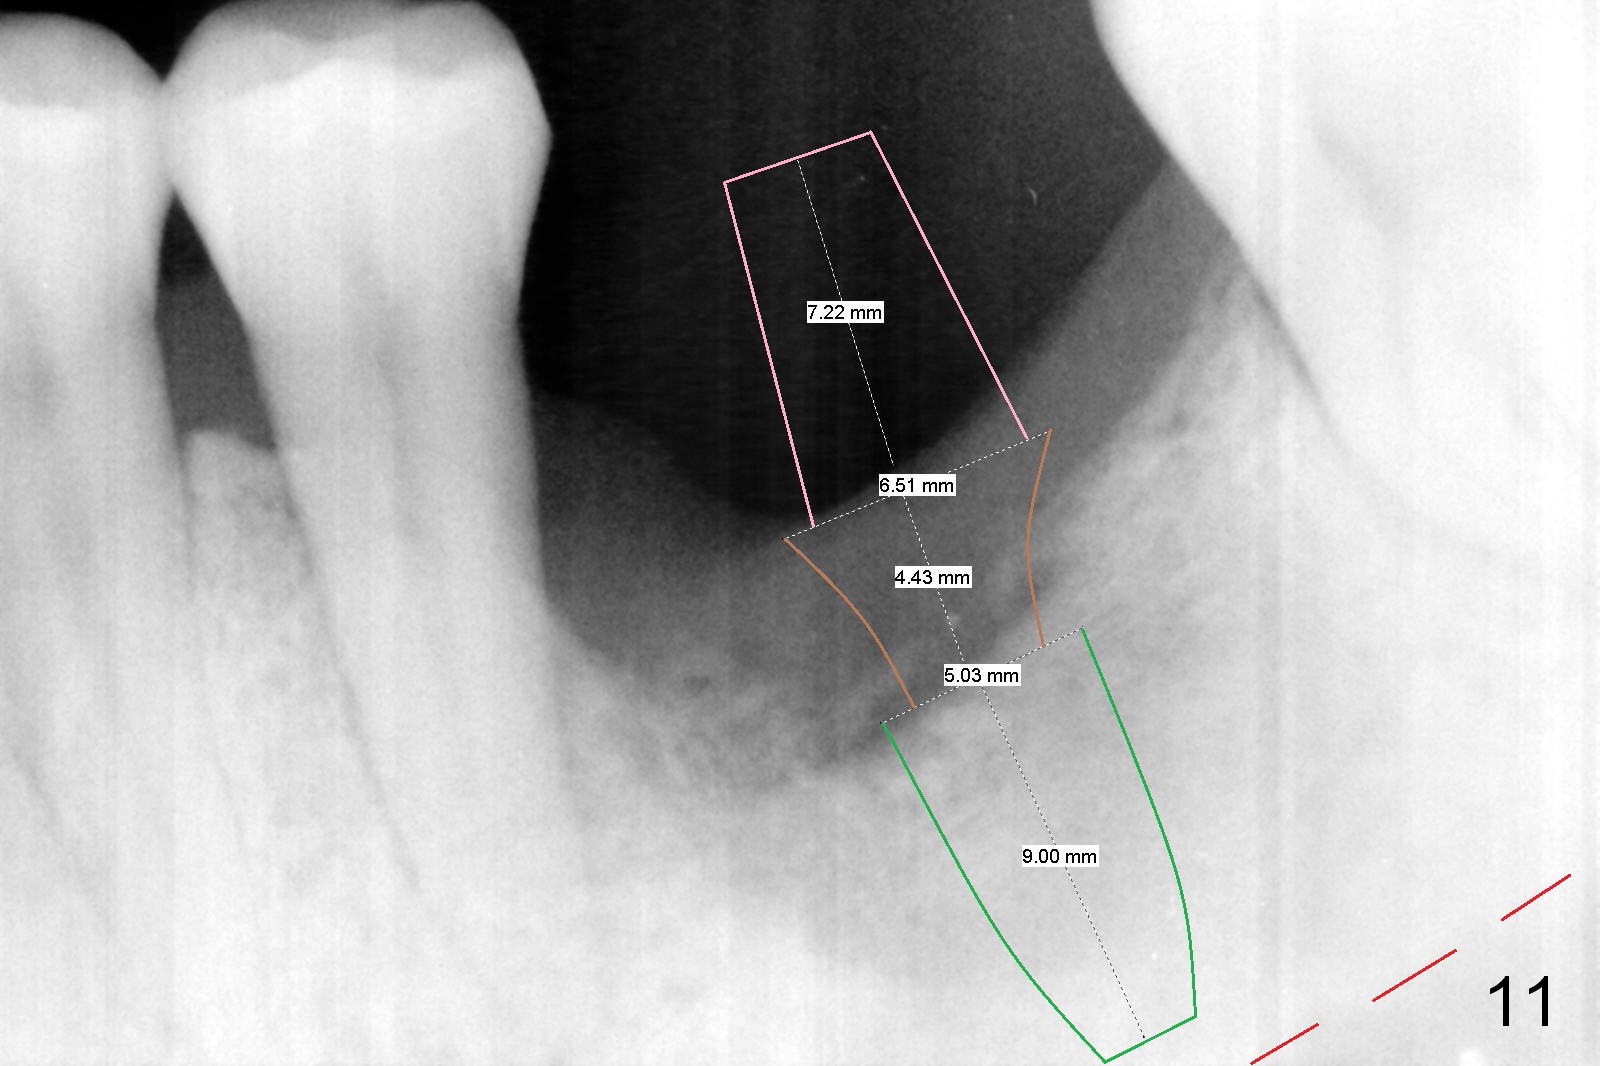

Considering the severe bone loss in the meisal socket, socket preservation is indicated if immediate implant is not feasible. Preop exam shows that the mesiobuccal gingival recession (Fig.1 MB) is not as severe as the mesiolingual one (Fig.2 ML). Because of oozing from the mesial socket, buccal envelop incision is made with flap raising to increase visibility. Probably due to periodontal infection, pain control is difficult. Osteotomy buccal to the Inferior Alveolar Canal proves to be risky. In addition, osteotomy in the mesial socket is more difficult than the distal one (Fig.3). Once the osteotomy depth is determined relative to the superior border of the Inferior Alveolar Canal (4 mm), the osteotomy depth increases by 2 mm. A 5.5x10 mm implant is placed with insertion torque ~ 35 Ncm (Fig.4); a 15 ° angled abutment (5.5 mm in diameter, 4 mm in cuff) is placed mesially. Then the abutment is turned lingually favorable for restoration (Fig.5), the remaining socket is filled with allograft/Osteogen (*) and Collagen Plug.

There is bone growth in the mesial socket 5 months post graft (Fig.10). Use Magic Split to get access and test bone density (which must be low or medium in the upper portion). Use drills beyond the socket if necessary. Crown/implant ratio is unfavorable (Fig.11); so progressive loading is essential.